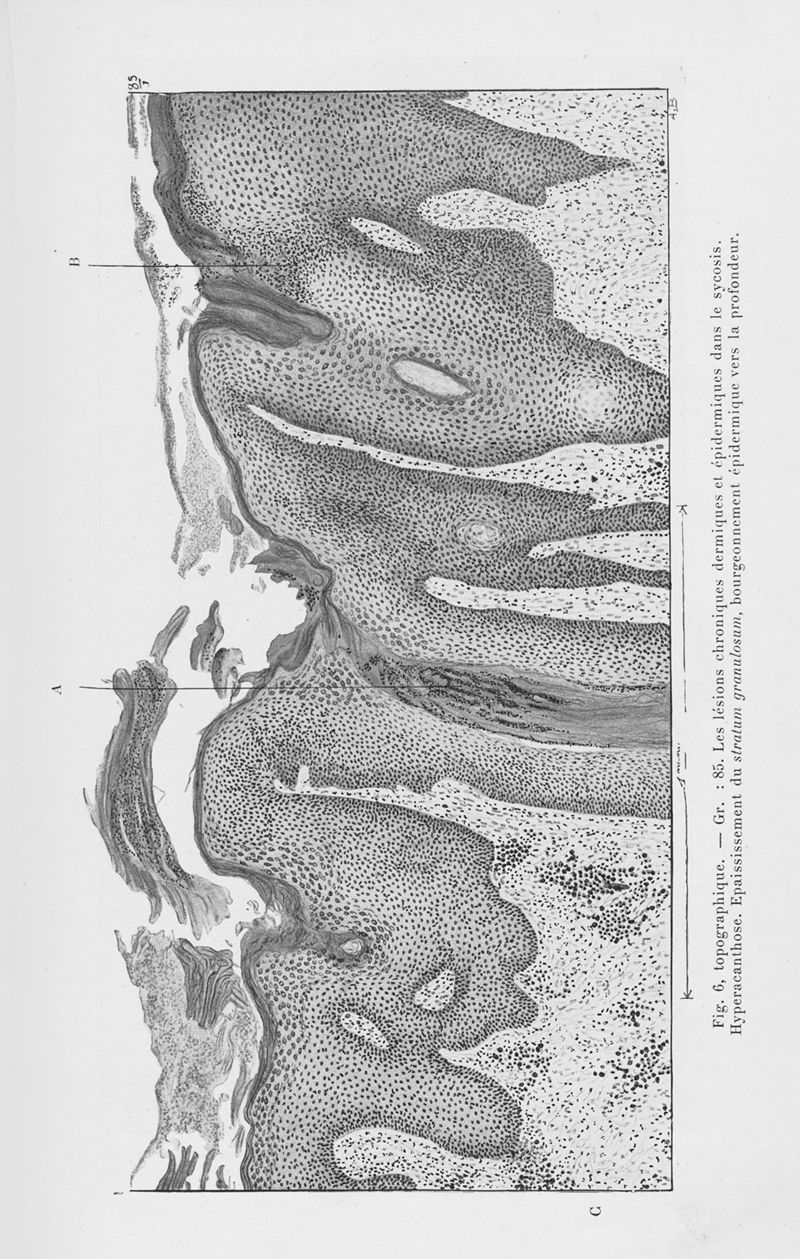

Annales de dermatologie et de syphiligraphie

6ème série, tome VII. - Paris : Masson, 1926.